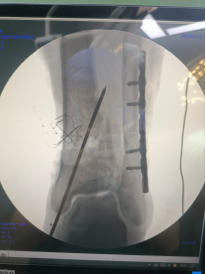

術(shù)中透視脛腓骨遠(yuǎn)端,予以克氏針臨時固定。

腓骨予以重建內(nèi)固定板固定。

三臂十一軸機(jī)器人輔助器牽引,安裝外固定架,透視檢查骨折端對位對線良好。